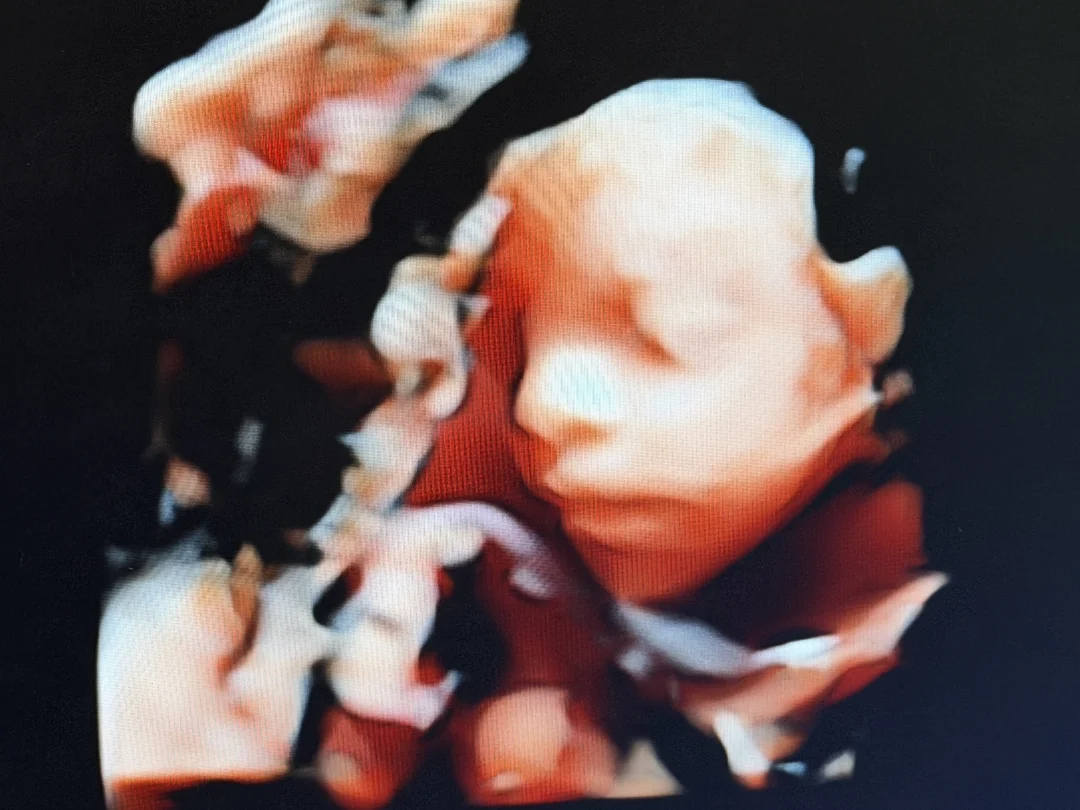

时间好快,转眼23周了!孕期